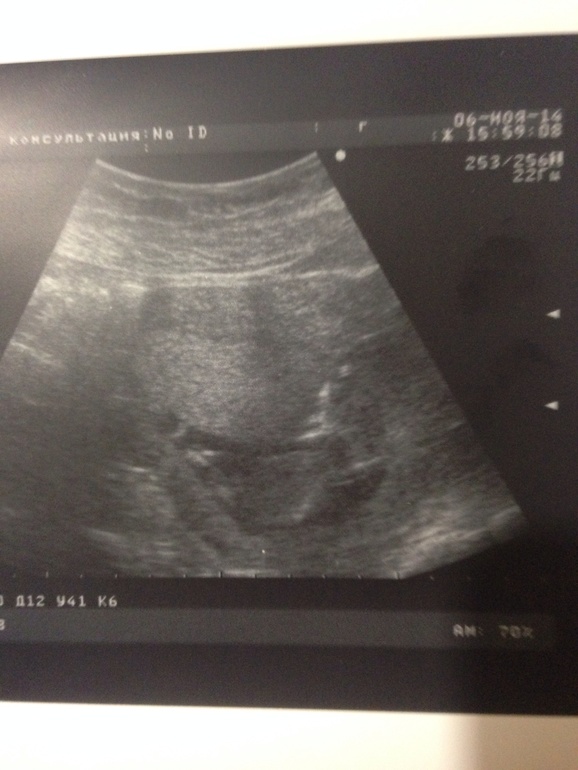

Сказать, что я переживала,- ну ничего не сказать! Переживания были в основном подсознательные : 2 ночи подряд я по раз десять ходила на скриниг ( во сне)))), а сегодня перед узи бешено колотилось сердце! Но все прошло просто замечательно)) ттт) увидела своего ребеночка) очень мило и трогательно) не буду мучатся с перечислением показателей и цифр) в общем мы рады и счастливы) фоточки под кат)))